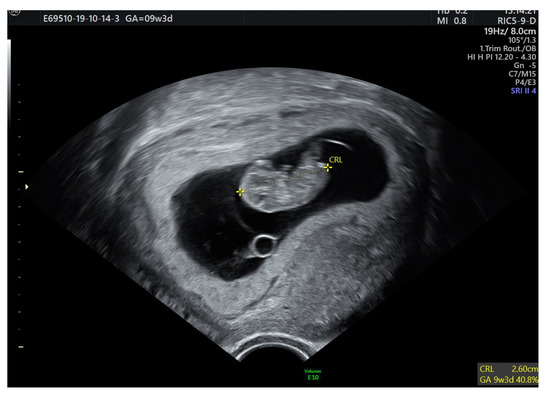

2. Case Report